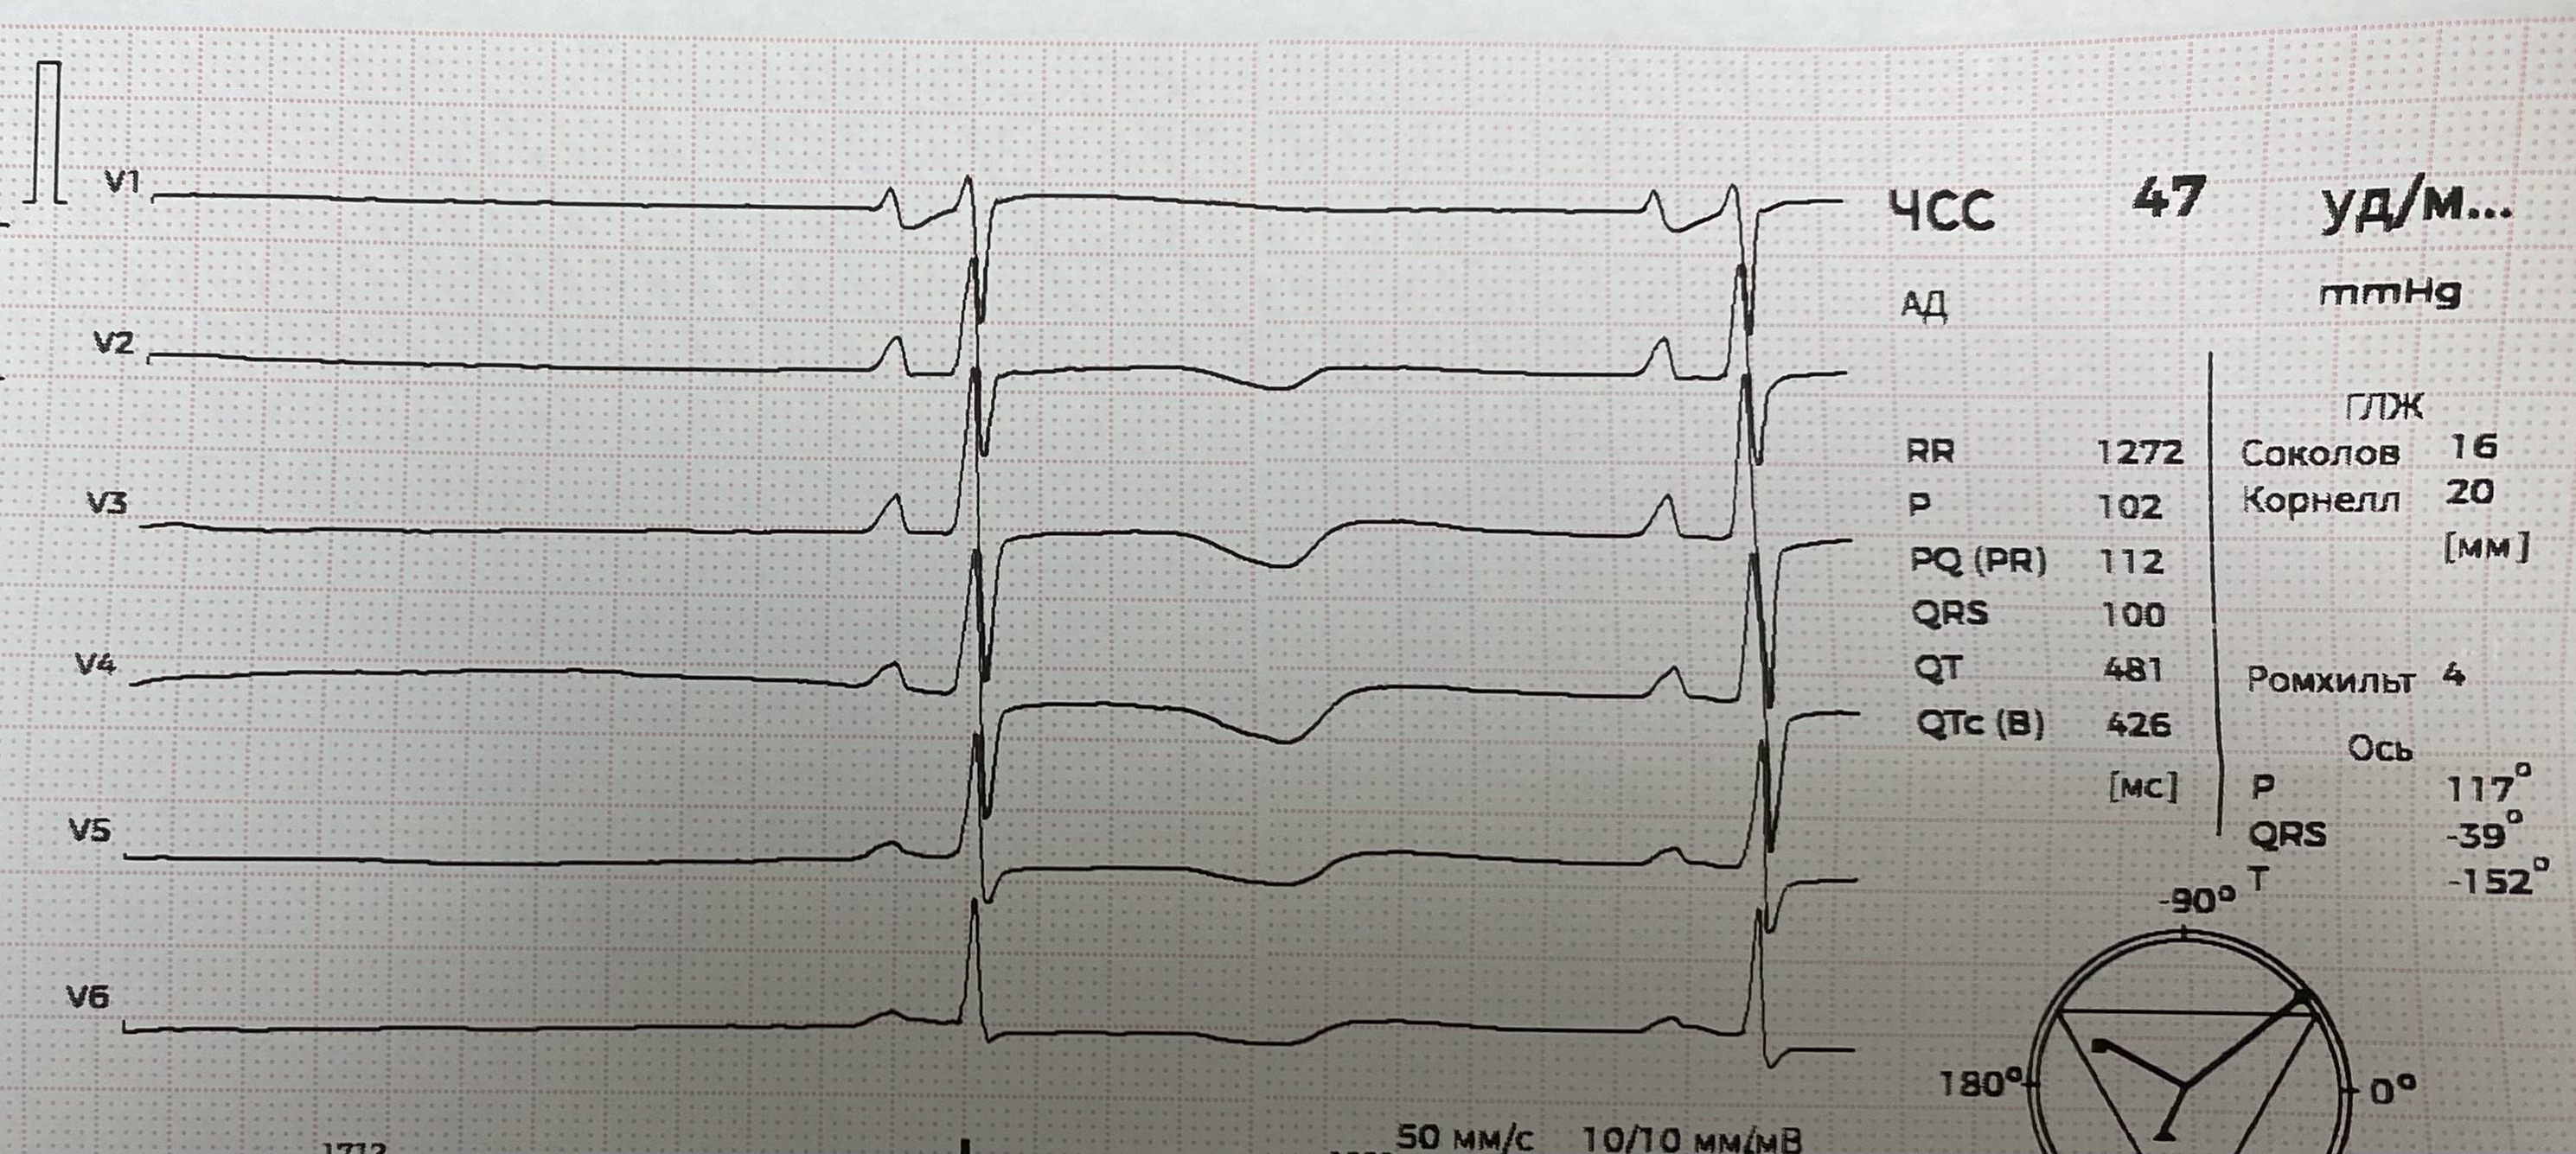

СА блокада

IMG_8980.JPG

IMG_8980.JPG [ 1013.55 KiB | Просмотров: 706 ]